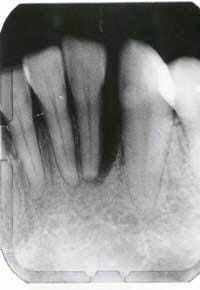

Patient usage has demonstrated dramatic improvements as is evident when comparing the initial probing results (Figure 2) with the after treatment results (Figure 3). The patient was a juvenile diabetic and suffered from periodontal disease for a number of years. The cost to the patient was substantially less than the cost of comparable conventional method and the results have been maintained.